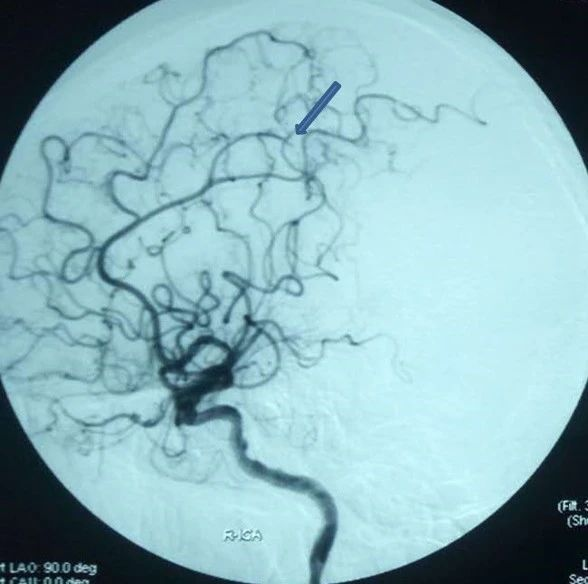

右侧颈内动脉造影显示MCA-M2段闭塞

蓝色箭头为M2血栓位置